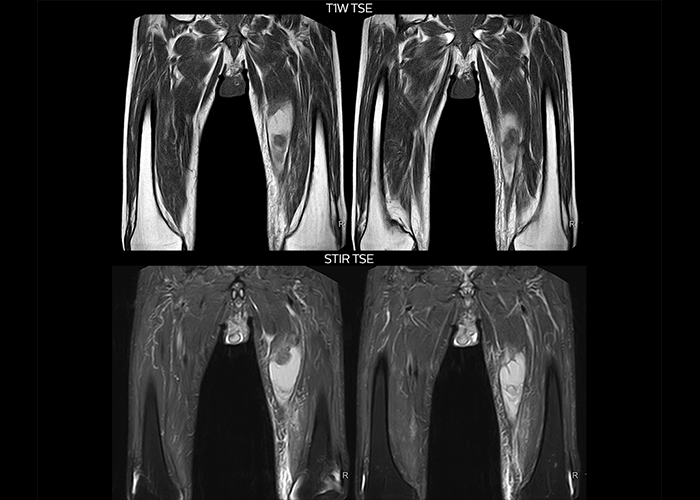

“To avoid coil changes we plan examinations of similar anatomies back to back, such as head and spine. Multiva helps us here a lot because coils don’t need to be changed frequently. Moreover, thanks to parallel imaging technology and 16-channel HeadSpineTorso and 8-channel MSK coils we are able to achieve excellent image quality. In this way Multiva helped us to increase both image quality and productivity.”

“Neurological cases, such as brain and spine imaging, represent the largest share in our MR scanning, followed by musculoskeletal cases. In general, we use simple and basic imaging protocols. But occasionally, we use advanced techniques for problematic cases if necessary.